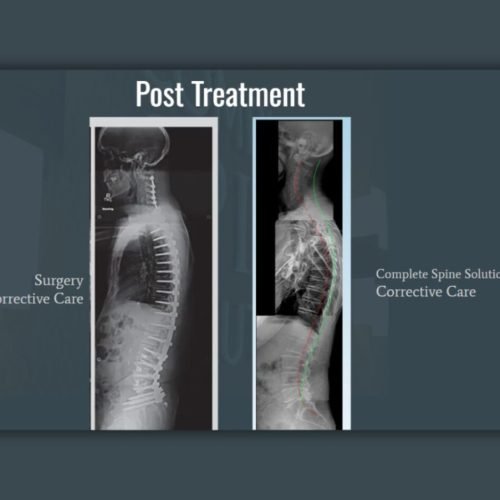

Our 99% Success Rate: How We Help Tucker Patients Avoid Spine Surgery

At Complete Spine Solutions in Tucker, GA, we’ve developed a comprehensive approach that has enabled less than 1 in 100 patients to require surgical referrals after starting care with us.

Our Advanced Certified Chiropractic BioPhysics (CBP) practitioners use a scientific, evidence-based approach that:

Through a personalized combination of precise spinal adjustments, targeted exercises, and traction-based care, we help Tucker patients achieve lasting relief and improved function, without the risks of spine surgery.

| Approach | RESTORES your spine’s natural alignment without cutting or permanently altering your body | DESTROYS healthy tissue – cuts, removes, or fuses spinal segments that can never be undone |

| Long-term Effects | STRENGTHENS your entire spine and prevents future problems | ACCELERATES spinal breakdown – creates new problems requiring additional surgeries |